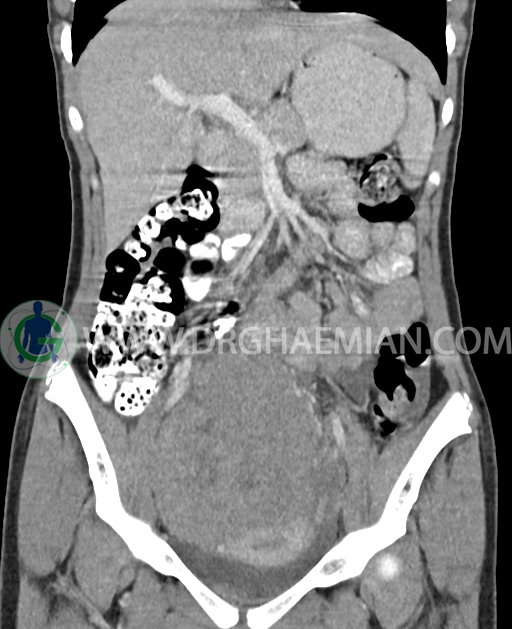

سی تی اسکن شکم و لگن از تشعشعات برای ایجاد تصاویر عرضی مقطعی از نایحه شکم و بین استخوان های لگن استفاده می کند. در این کیس تومور سلول زایا به ابعاد mm 125 x 112 x 80 دیده می شود.

در سی تی اسکن اسپیرال شکم و لگن با کنتراست خوراکی و وریدی (مولتی دیدکتور 16 با مقاطع ظریف و بازسازی های ساژیتال و کرونال) :

توده هیپردنس لوبوله بزرگ به ابعاد 125x112x80mm حاوی نواحی سیستیک داخلی و enhancement قابل توجه پریفرال همراه با آسیت متوسط در فضای شکم و لگن با احتمال بیشتر با منشا از تخمدان راست، درون لگن دیده می شود که در درجه اول مطرح کننده germ cell tumor می باشد .